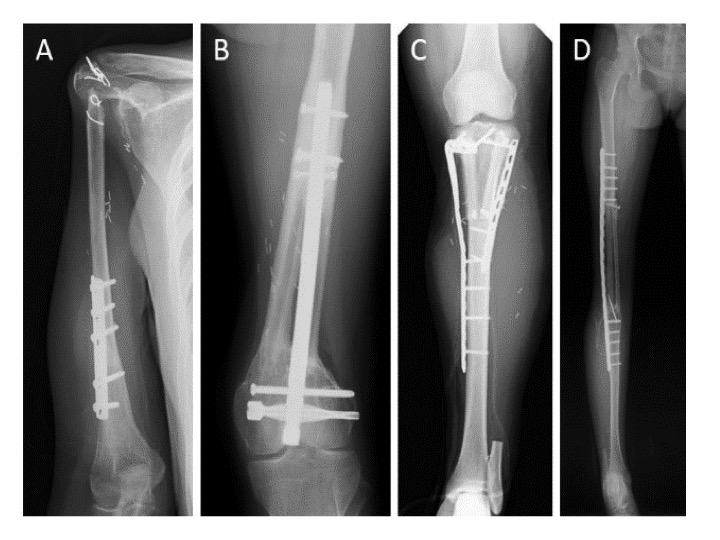

・マイクロサージャリーを用いた自家組織再建を積極的に行っています。

当院救急部の高橋信行助教と千葉充将助教とともに、腫瘍切除後の巨大骨欠損に対して、多くの血管柄付き腓骨移植(vascularized fibular grafts: VFGs)を用いた再建を行っています。VFGsは一度癒合すれば、人工関節と異なり無菌性のゆるみや感染などの合併症はほとんどなく、機能は生涯保たれます。生涯続く再建を目指し、VFGsを再建法として使用しています。

Emori M, et al. Vascularised fibula grafts for reconstruction of extremity bone defects after resection of bone and soft tissue tumours: A single-institutional study of 49 patients. Bone Joint J. 2017